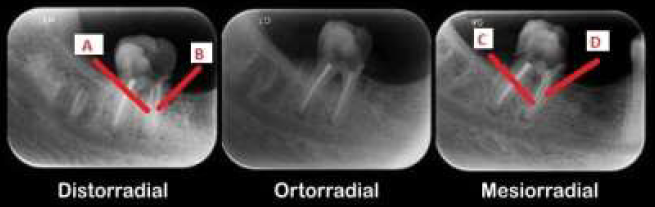

A técnica de Clark tem como objetivo identificar a localização de algumas estruturas da cavidade bucal. Analise a imagem e responda as questões 21 e 22.

enunciado 1892958-1

Assinale a alternativa correspondente a análise coerente das assertivas.

I. O canal C está pela lingual e o D pela vestibular.

PORQUE

II. A estrutura que se encontra na frente, acompanha o movimento do feixe de raio X.

enunciado 1892957-1

Analise as assertivas:

I. O canal A está pela lingual, enquanto o B está por vestibular.

II. O canal A está pela vestibular, enquanto o B está por lingual.

III. O canal D está pela vestibular enquanto o canal A está por vestibular.

O canal C está pela vestibular, enquanto o B está por vestibular.